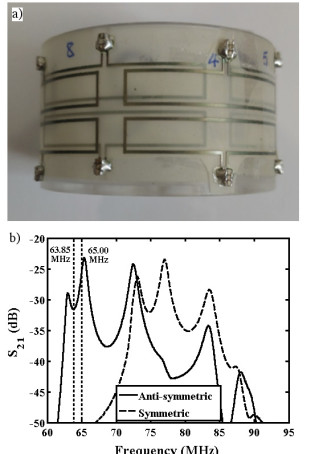

We have demonstrated an early prototype implantable sensor for monitoring surgical wounds after bowel reconstruction. The sensor consists of a coupled pair of 8-element magneto-inductive ring resonators, designed for mounting on a biofragmentable anastomosis ring to give a local increase in signal-to-noise ratio near an annular wound during 1H magnetic resonance imaging. Operation on an anti-symmetric spatial mode is used to avoid coupling to the B1 field during excitation, and a single wired connection is used for MRI signal output. The electrical response and field-of-view have been estimated theoretically. Prototypes have been constructed from flexible elements designed for operation at 1.5 T, electrical responses have been characterized and local SNR enhancement has been confirmed using agar gel phantoms.

| Electrical arrangement of a) single and b) double magneto-inductive ring resonators. |

| Prototype sensor: a) arrangement of thin film circuits before encapsulation; b) mode spectrum obtained by inductive probing. |